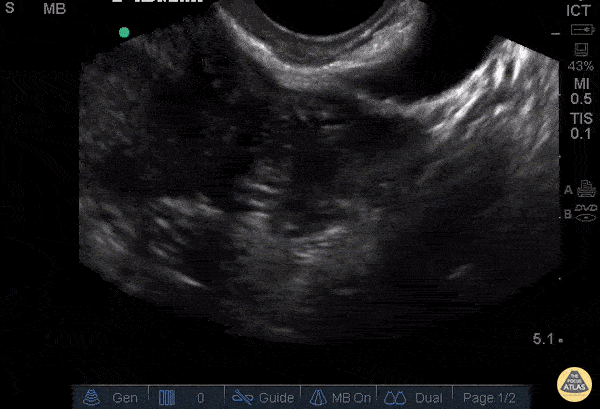

31 y/o G1P0 presenting at unknown gestational age for pelvic pain and vaginal bleeding. Described increasing vaginal bleeding for 7 days and intermittent sharp lower abdominal and pelvic pain, mostly left sided, 6/10 in severity. Pelvic exam was significant for cervical motion tenderness and left adnexal tenderness. Pelvic ultrasound shows left adnexal complex heterogeneous structure and associated free fluid in the pelvis. Patient underwent diagnostic laparoscopy with left salpingectomy for left tubal ectopic pregnancy. Stacey Frisch, MD Aleksandr Gleyzer, MD - Kings County/SUNY Downstate Emergency Medicine